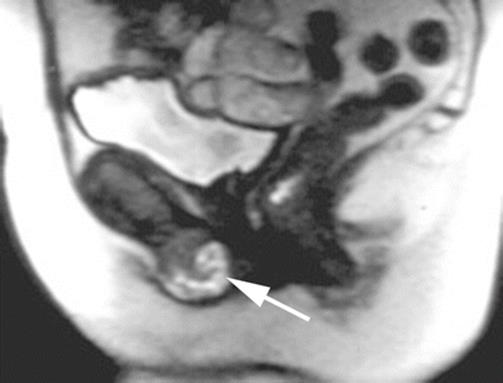

Fig. 8.35

A coronal MRI shows the presence of a solid, well-circumscribed mass of the perineum (arrow)